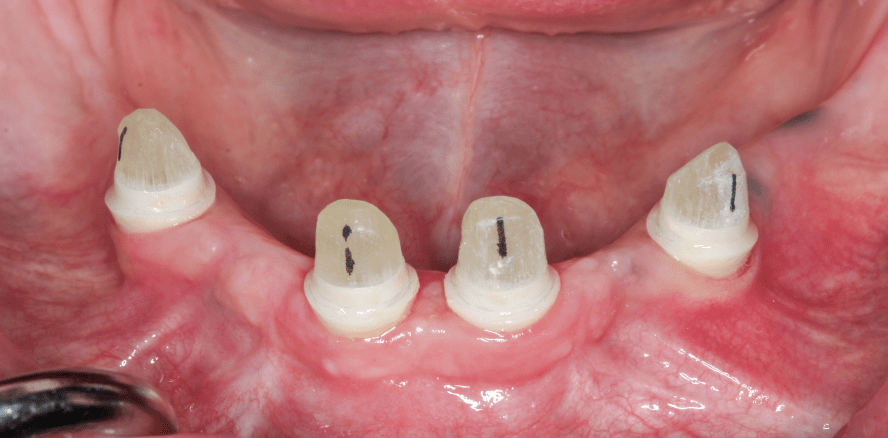

Um die Bakterienbelastung zu reduzieren und folglich die Weichgewebeverhältnisse für den chirurgischen Eingriff zu verbessern, wurde im Vorfeld eine dreimonatige Prophylaxebehandlung durchgeführt. Die insuffiziente Brücke wurde zunächst in vier Teile zerlegt und entfernt, bevor alle Zähne des Unterkiefers extrahiert wurden (Abb. 4). Hiernach wurden die Knochenqualitäten um die Alveolen bestimmt und die Implantate gemäß dem entsprechenden chirurgischen Protokoll bis zu einem finalen Drehmoment von 25 Ncm lappenfrei inseriert (Abb. 5 und 6). Die provisorische Vollprothese, die auf Grundlage eines konventionellen Abdrucks im Vorfeld hergestellt worden war, wurde unterfüttert, um die einheilenden Implantate nicht durch unerwünschte Belastung zu stören, und dann eingesetzt.

Nach dreimonatiger Heilung wurde mittels Periotest die erfolgreiche Osseointegration der Implantate festgestellt (Abb. 7). Der Unterkiefer wurde einschließlich der Implantatschultern und Innenverbindungen konventionell abgeformt und im Dentallabor ein Gipsmodell hergestellt. Auf diesem wurden die Glasfaserstifte, die als prothetisches Retentionselement des Implantatsystems fungieren, präpariert (Abb. 8 und 9). Der korrekte Sitz der präparierten Stifte in den Innenverbindungen der Implantate wurde intraoral überprüft (Abb. 10), um mit der Herstellung des Stegs fortfahren zu können. Nach Herstellung wurde auch dessen Sitz intraoral überprüft (Abb. 11). Anschließend wurde die Deckprothese hergestellt. Die Matrize, die als sekundäres Retentionselement auf der Innenseite der Prothese integriert wurde, war aus PEEK gefertigt (Abb. 12). Glasfaserstifte und Steg wurden mit einem dualpolymerisierenden Zement adhäsiv befestigt (RelyX Unicem 2, 3M; Abb. 13) und die Deckprothese eingesetzt (Abb. 14), um Funktion und Ästhetik wiederherzustellen.